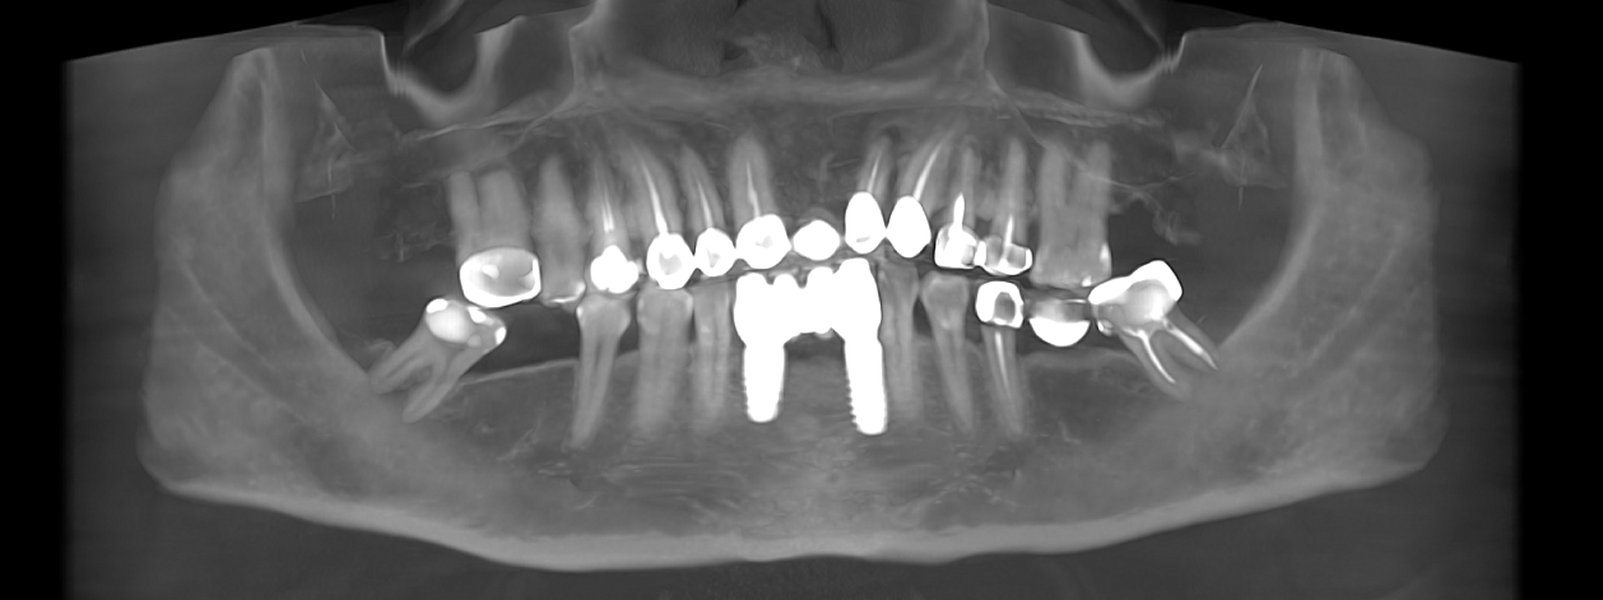

Tomografii (CBCT)

Caz 2